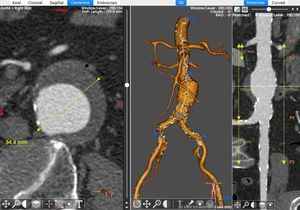

EndoSize® es un

software de

planificación endovascular y dimensionado de dispositivos diseñado para la

planificación

preoperatoria de intervenciones vasculares ...